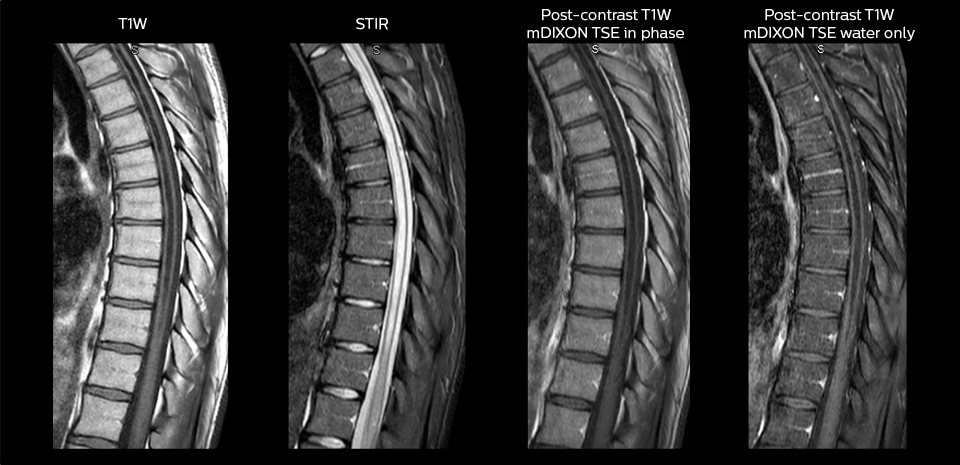

“We use mDIXON TSE extensively in our spine imaging in the emergency room,” says Dr. Karis. “It’s particularly nice in that it is very robust with regard to susceptibility type of problems that would come up with traditional spectral fat-saturated images; these problems are essentially eliminated with the mDIXON technique. In our ED environment it’s really nice to have the fat-free imaging that goes along with the mDIXON technique.

“For the thoracic and cervical spine routine non-contrast exam, for example, we perform one mDIXON T2 TSE sequence, which provides us with two outputs: the fat-and-water-together T2-weighted images, as well as the water-only sagittal T2-weighted images. And then we also perform an axial gradient echo exam.”